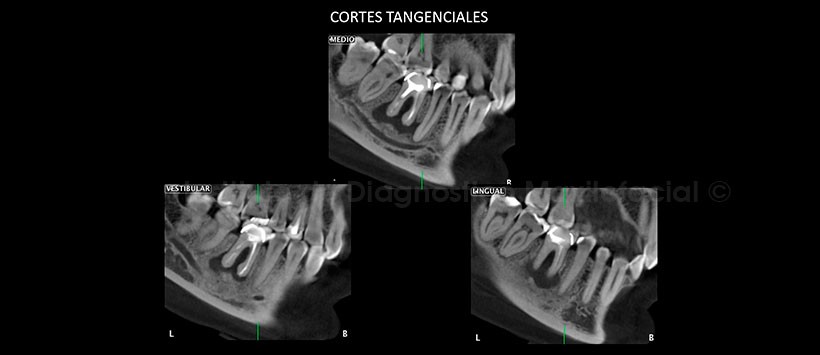

A la evaluación de la tomografía volumétrica (CBCT) en cortes axiales (Figura 2), transaxiales (Figura 3) y tangenciales (Figura 4) Proceso osteolítico perirradicular de limites difusos que compromete reborde alveolar de las piezas 4.5, 4.6 y 4.7 con aumento de la densidad ósea circundante sugestiva de Osteomielitis Esclerosante Focal.